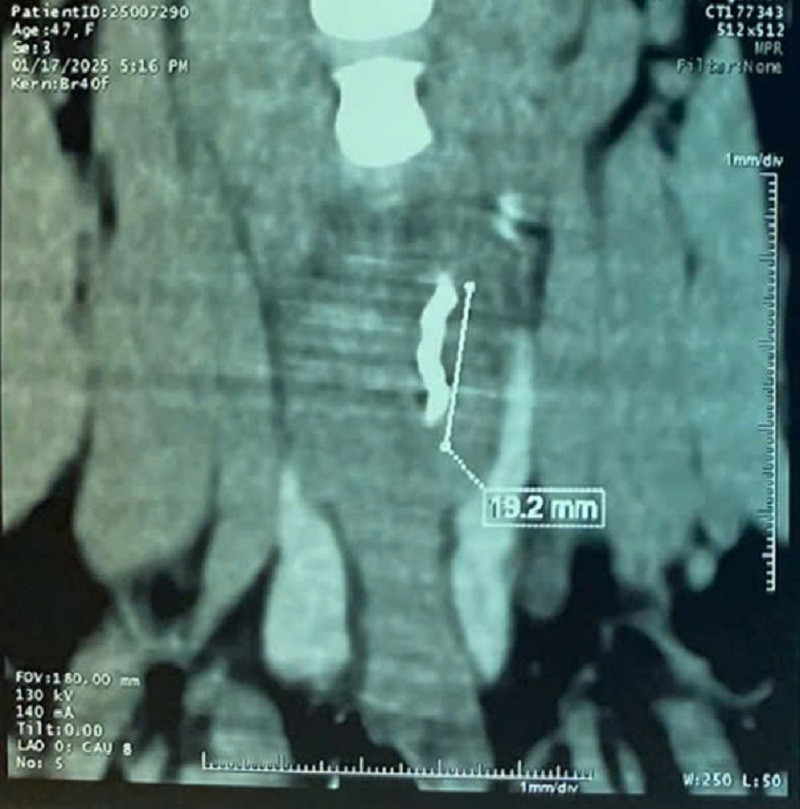

Ngay sau trường hợp trên, một trường hợp khác là nữ bệnh nhân 47 tuổi, ngụ tại Bình Phước cũng nhập viện sau khi nuốt đau. Trước đó, bệnh nhân đã đến thăm khám và uống thuốc ở một bệnh viện tư nhưng không hiệu quả. Theo bệnh sử, cách nhập viện 10 ngày, người này nuốt đau sau khi ăn cơm với cá kho nên nghĩ mình bị hóc xương.

Bệnh nhân đến khám bệnh viện tư, được nội soi nhưng không thấy dị vật. Các bác sĩ đã cho thuốc uống nhưng bệnh không thuyên giảm, cơn đau tăng dần. Tại Bệnh viện Tai Mũi Họng TPHCM, bệnh nhân được CT-scan cổ phát hiện dị vật dài hơn 20mm ở miệng thực quản, đứng dọc, ngang mức đốt sống cổ C5. Ê kíp các bác sĩ đã tiến hành phẫu thuật nội soi thanh quản ống cứng lấy dị vật là mảnh kim loại dài 20mm dưới niêm mạc miệng thực quản. Sau phẫu thuật cả hai nữ bệnh nhân đều đã ổn định sức khoẻ.

| Dị vật là mảnh kim loại nằm ở vị trí rất khó phát hiện được nhìn thấy trên hình ảnh kiểm tra |